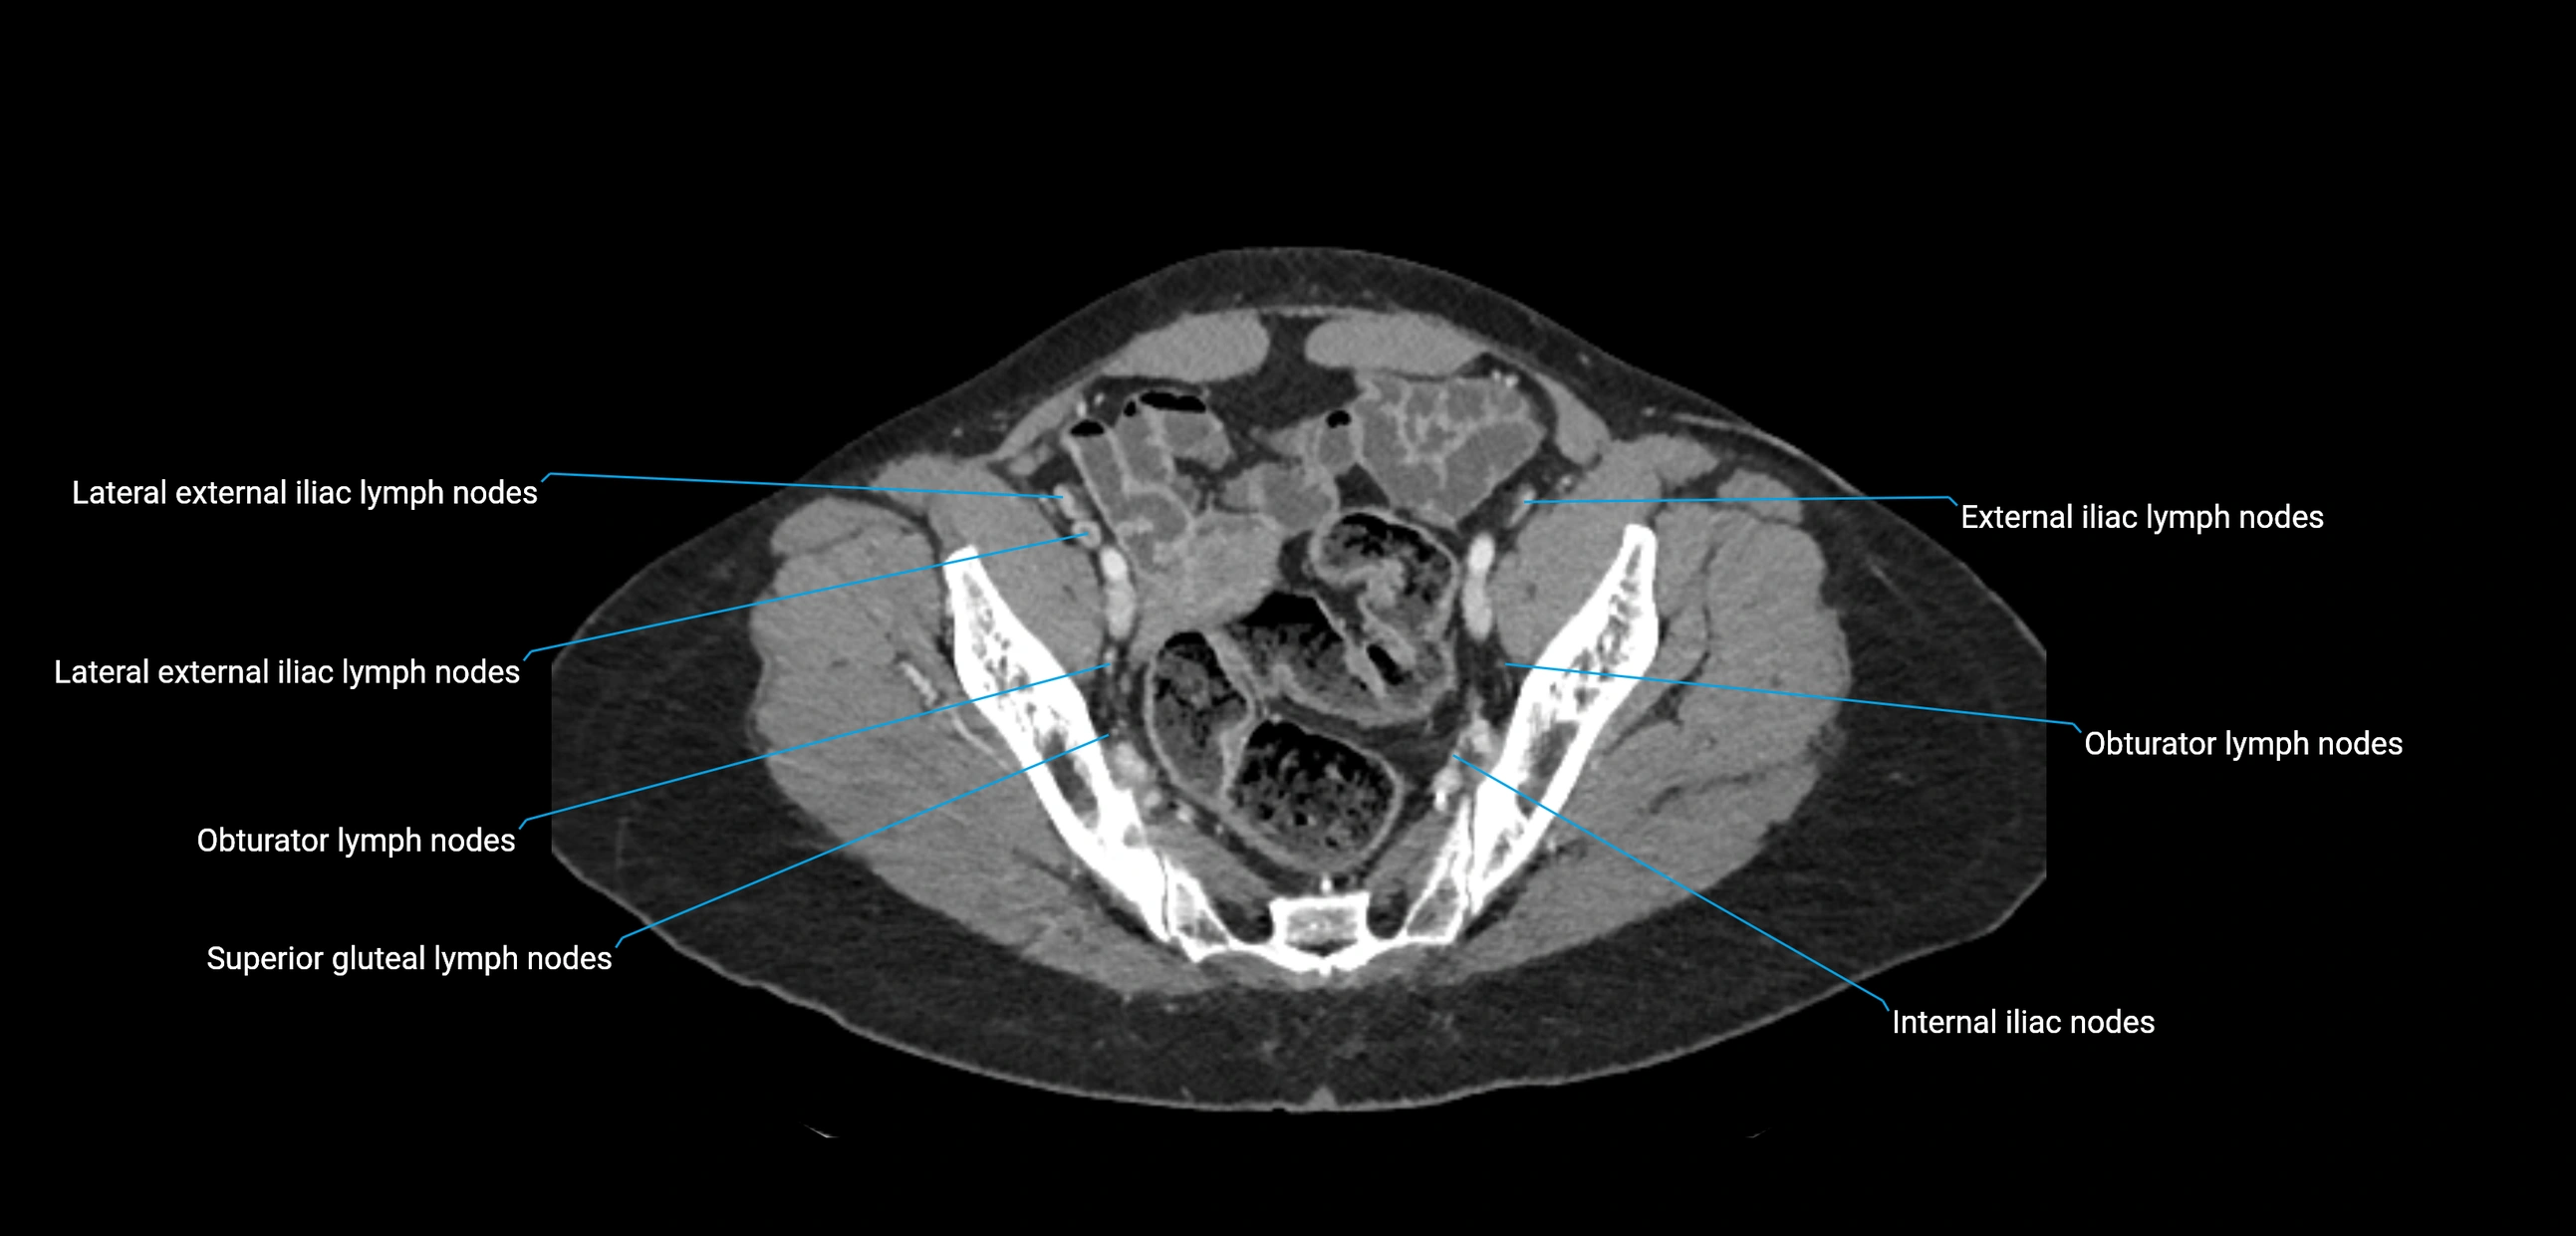

CT image

image